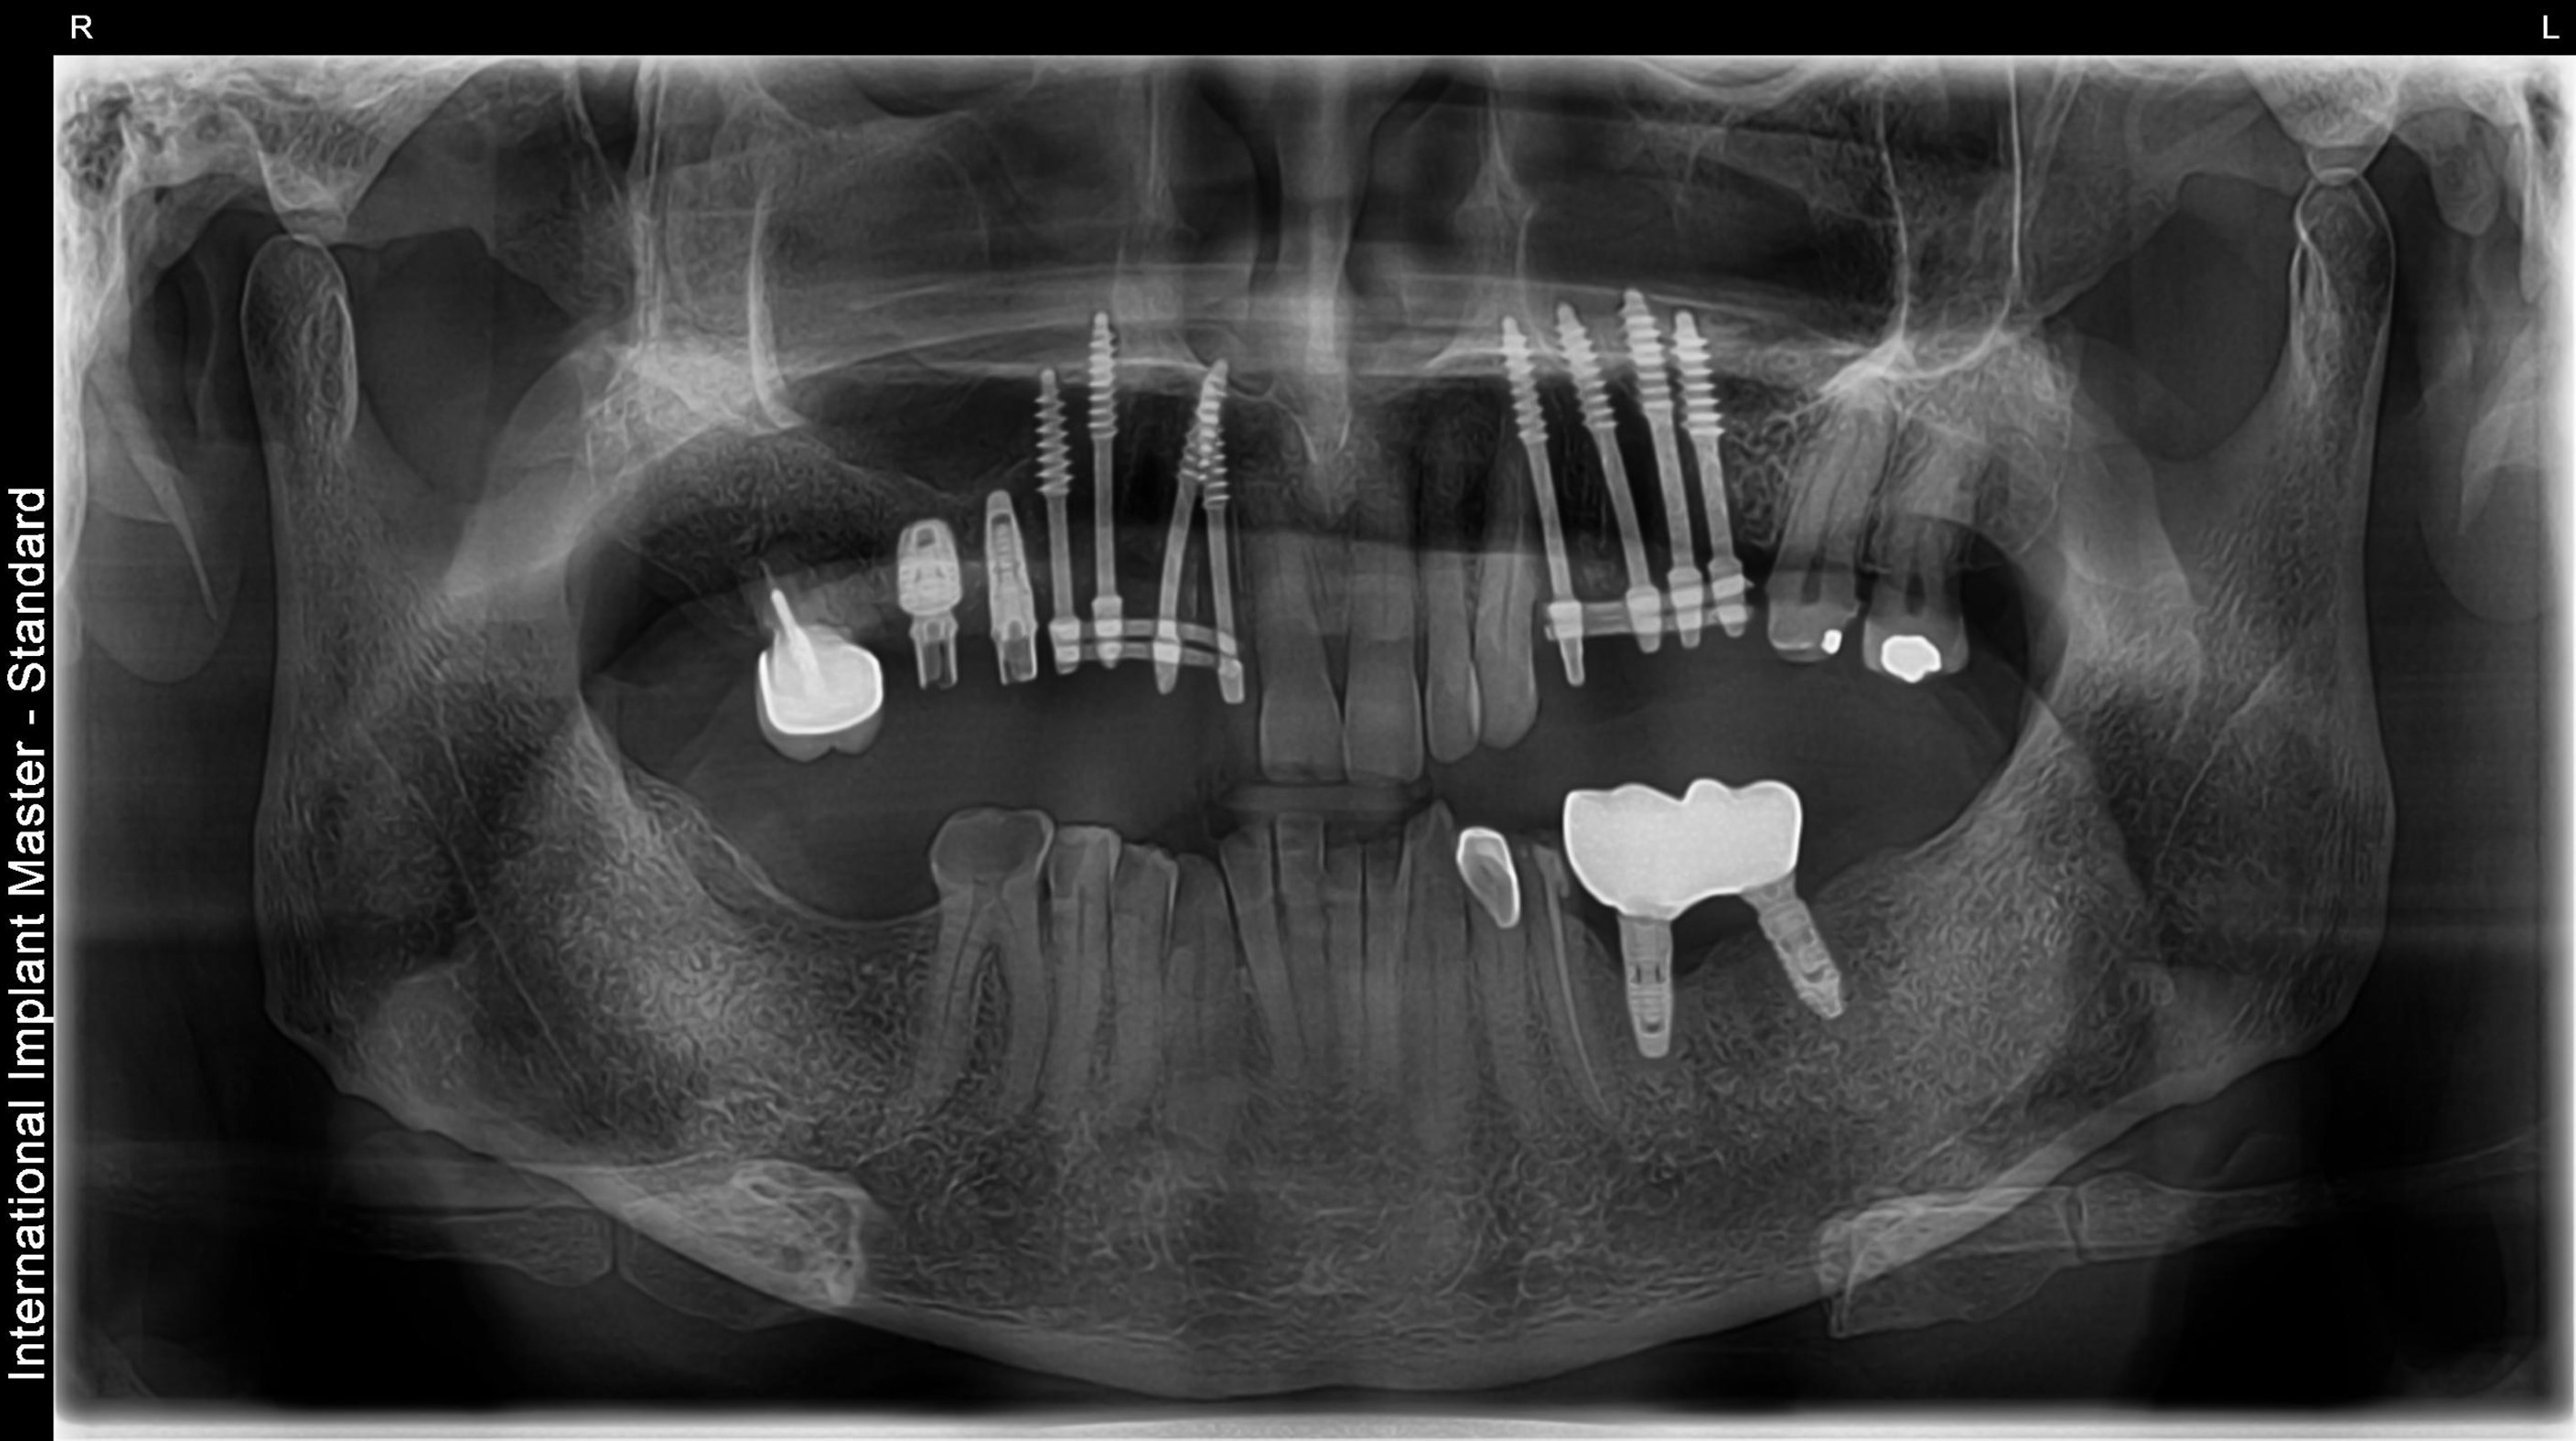

Full Mouth Rehabilitation

This includes comprehensive dental work such as implants, crowns, root canals, and other restorations to fully restore dental health and aesthetics.

Before vs After Xrays